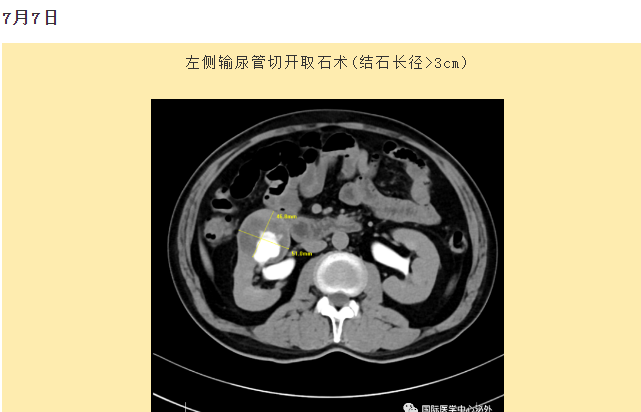

西安國(guó)際醫(yī)學(xué)中心醫(yī)院順利完成了達(dá)芬奇Xi(第四代)機(jī)器人裝機(jī)。7月6日—7月15日,泌尿外科成功完成了達(dá)芬奇Xi(第四代)機(jī)器人手術(shù)6例,標(biāo)志著科室微創(chuàng)外科邁入新時(shí)代,造福萬(wàn)千患者。